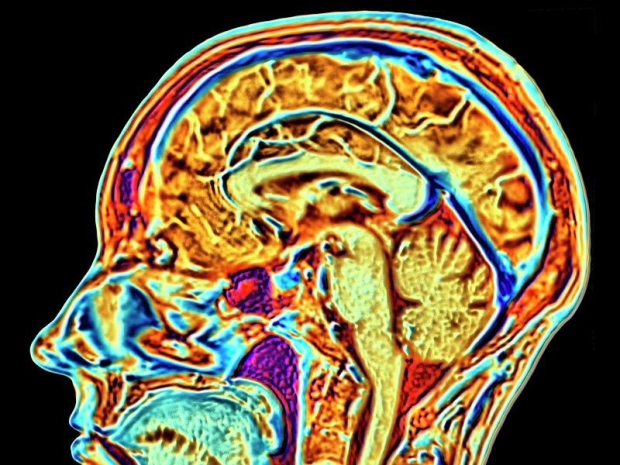

The firm aims to link human brains to computers and wants to help sort out tricky brain problems.

This lets them start the six-year study where a robot is used to stick 64 bendy threads, thinner than a human hair, onto a part of the brain that controls movement.

The firm says that these threads let its trial implant - powered by a battery that can be charged without wires - record and send brain signals to an app that works out how the person wants to move.